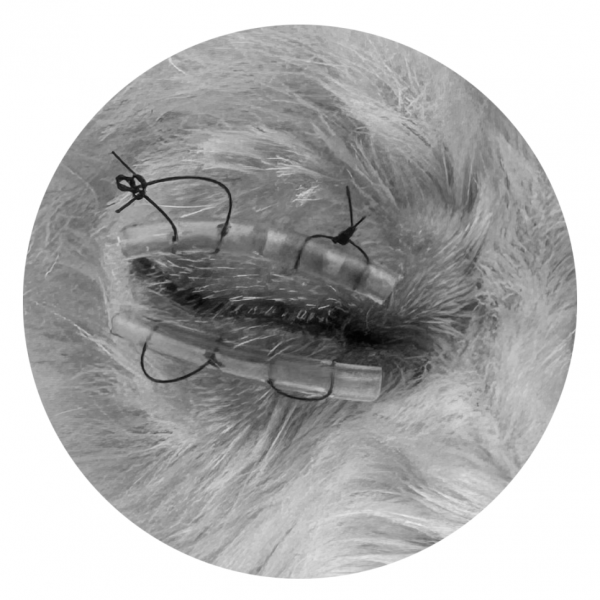

→ 재탈구 방지를 위해 안검봉합술 진행

특히 강아지의 경우,

안구돌출 시 medial rectus muscle 손상에 의한 외사시가 흔하기 때문에,

안구 안정화를 위해 안검봉합술을 진행하였습니다.

이후 약 2주간 치료를 진행했고, 회복 후 봉합은 제거했습니다.